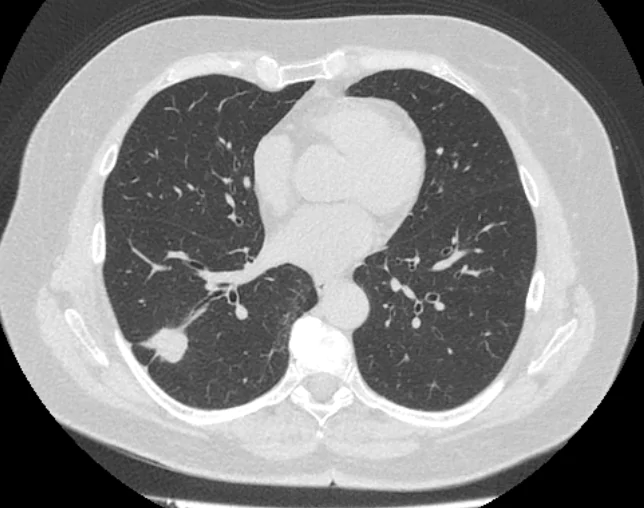

Что можно увидеть на КТ при раке легких? На традиционной компьютерной томографии, без введения контрастных агентов, можно увидеть характер, структуру и локализацию средних и крупных опухолевых очагов. Без введения контрастных агентов на ранних стадиях, выявление метастазов и мельчайших опухолевых очагов является затруднительным. Согласно КТ легких можно установить следующее:

-изменения в размерах и форме легкого;

-размеры и точную локализацию опухолевого очага;

-количество опухолевых очагов;

-наличие крупных метастазов в близлежащих тканях и органах грудной полости;

-поражение или изменения структуры соседних тканей.